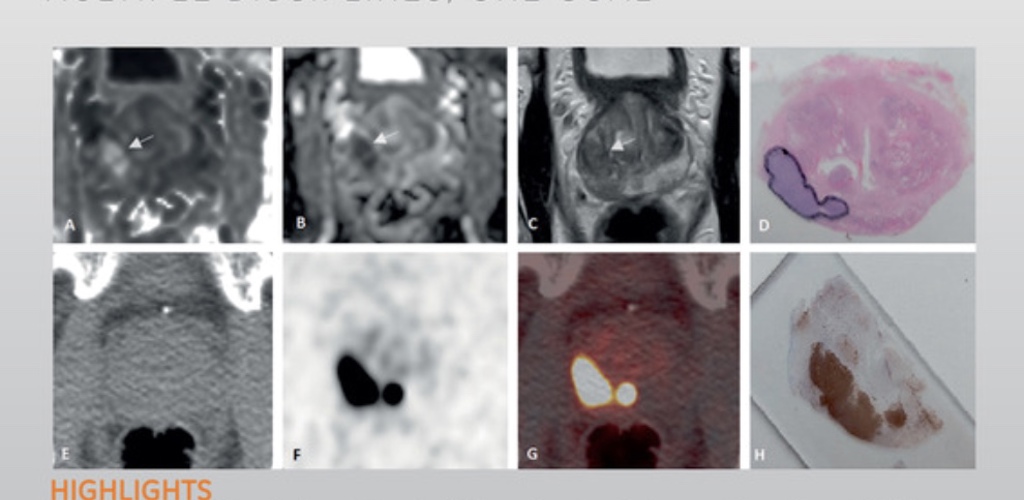

European Urology Oncology tillhör den europeiska urologifamiljen och är den första tidskriften inom EAU som är dedikerad till studiet av maligniteter i genitourinära sjukdomar.

Du kan läsa senaste tidskriften volym 6, nummer 6 här på European Urology Oncologys webbplats.